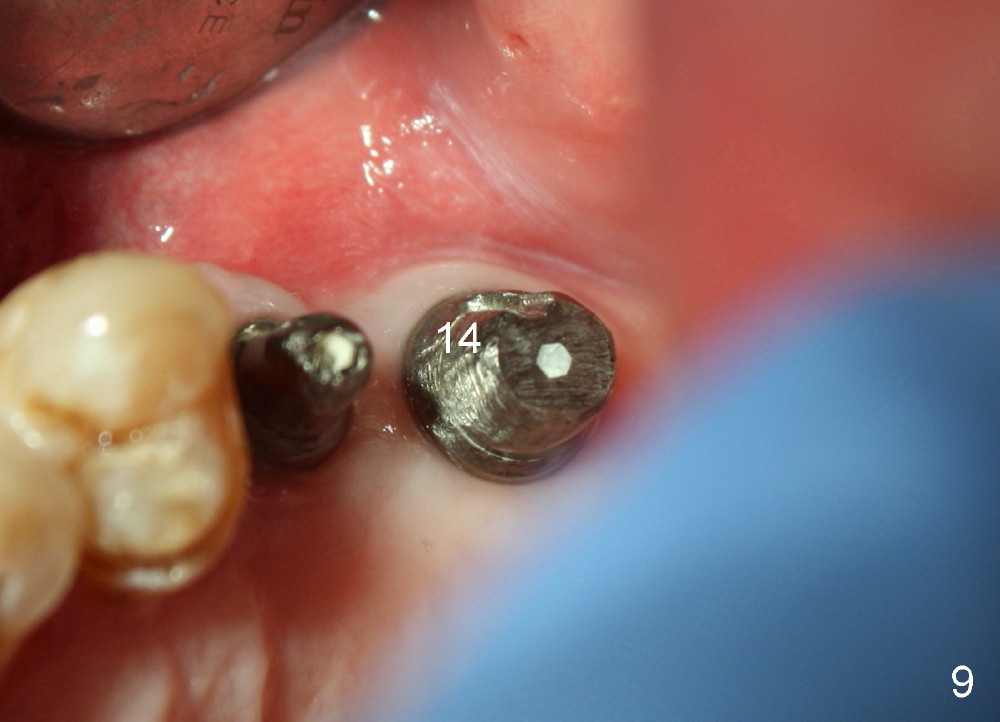

Bone graft remains in place 2 months postop (Fig.7 arrowheads); its density increses 4 months postop (Fig.8). The gingiva around the implant and abutment at the site of #14 is healthy (Fig.9 (4 months postop before final impression);10 (5 months postop immediately before final cementation)).